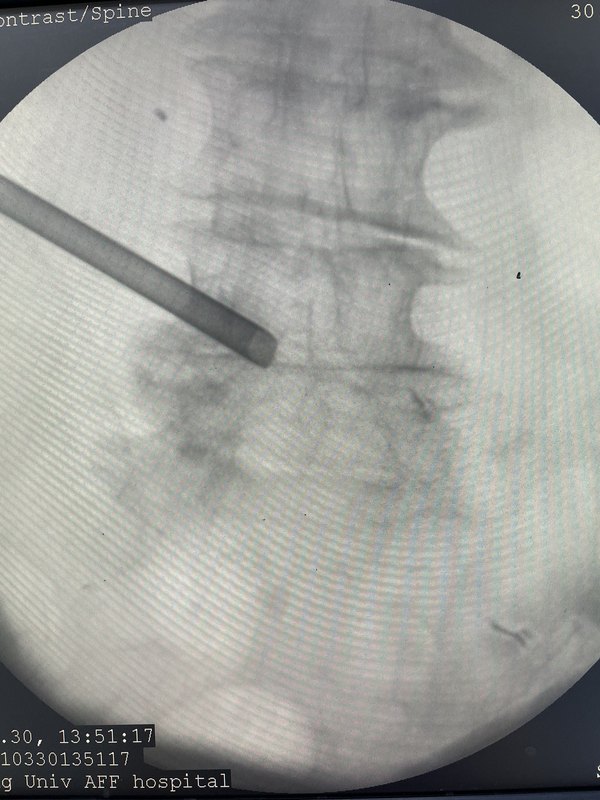

- 椎間孔鏡治療85歲老爺子腰椎間盤突出癥椎間孔狹窄

男性,85歲,腰痛,伴左腿疼痛2個(gè)月,經(jīng)過多方保守治療效果很差,已經(jīng)無法下地行走,在床上翻身都已經(jīng)很困難,下定決心來了我們醫(yī)院做手術(shù)。經(jīng)過嚴(yán)格的術(shù)前的準(zhǔn)備,而且我們還做了封閉,做的封閉四腰45左側(cè)的神經(jīng)根管封閉,明確責(zé)任節(jié)段,經(jīng)過3天的觀察,癥狀再次出現(xiàn),認(rèn)為封閉療效是暫時(shí)的,決定在局麻下行椎間孔擴(kuò)大成形和腰45椎間盤摘除術(shù),手術(shù)后病人的癥狀明顯緩解第二天下地已經(jīng)沒有任何困難,所以認(rèn)為封閉是一個(gè)好辦法,明確了責(zé)任的節(jié)段,椎間孔鏡手術(shù)對于這種高齡的人員還是比較適合的!